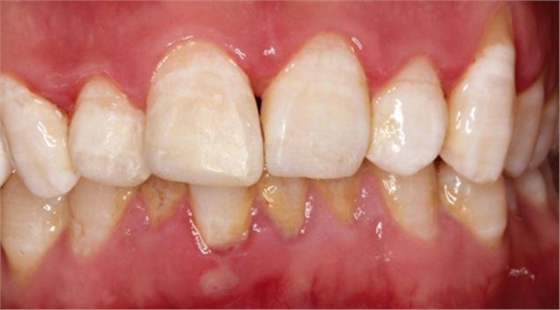

患兒8歲,不慎摔倒導(dǎo)致上前牙折斷,來(lái)院就診,行根尖片檢查,根尖孔尚未閉合,且呈喇叭口狀,就診時(shí)患兒自己帶來(lái)了折裂的牙齒碎片,口內(nèi)檢查,A1折斷1/2,斷端可見(jiàn)兩處 露髓點(diǎn),一處直徑約為1.5mm,一處約為1mm,未見(jiàn)明顯出血,B1近中切角缺損,考慮到患兒根尖孔尚未閉合,于是決定保留牙髓(若根尖孔已經(jīng)閉合,則摘除牙髓,纖維樁加強(qiáng)粘結(jié)固定折裂碎片。不多說(shuō)了,還是看術(shù)前照片: